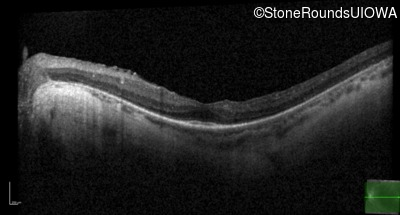

Optical Coherence Tomography - Left - 20/50 +2

Exemplar / OCT Stack

OCT Stack